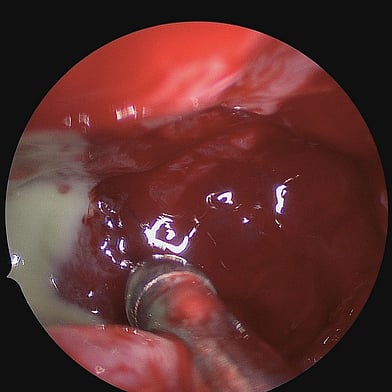

Diagnosing chronic rhinosinusitis involves a comprehensive evaluation, which may include medical history and physical examination, nasal endoscopy, imaging studies, allergy testing, and conducting nasal and sinus cultures.

Treatment can be initiated with regular medications like nasal steroid sprays, anti-histamine tablet and sprays, antibiotics, nasal saline sprays, or oral corticosteroids. But specific problems causing rhinosinusitis may be treated with Functional Endoscopic Sinus Surgery (FESS).